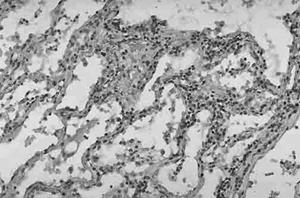

顯微鏡下的小腸結腸炎耶爾森菌肺炎症狀實驗室檢查:血或痰培養可陽性。痰中可發現革蘭陰性桿菌。當有咽部感染時,咽部分泌物可發現致病菌。化膿性結節、腹水、關節腔積液標本有可能發現致病菌。